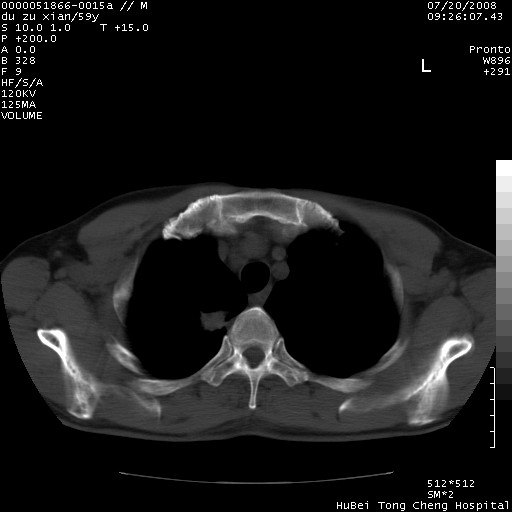

以下是引用宇宙ct在2008-8-25 23:21:00的发言:[br]右肺周围性肺癌并肋骨转移,纵隔淋巴结转移。

以下是引用zsl6918在2008-8-25 22:40:00的发言:[br]右肺周围性肺癌并肋骨转移,纵隔淋巴结转移。

以下是引用zy_zj在2008-8-26 15:24:00的发言:[br]单从病变本身,我倾向良性炎性病变,但肋骨转移了,所以说是考虑右肺周围性肺癌并肋骨、纵隔淋巴结转移可能性大。